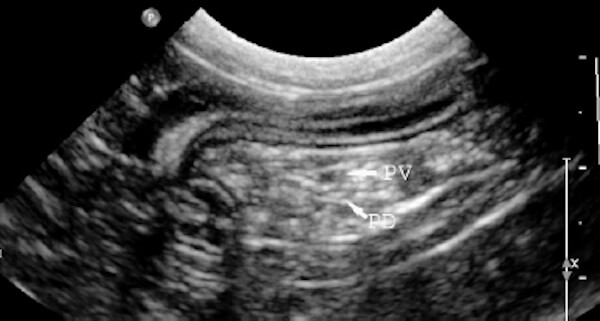

Pancreasul este o glanda cu o functionare duala, care se afla in partea anterioara a abdomenului, chiar sub stomac, langa partea superioara a intestinului subtire. Acesta indeplineste doua functii importante: l endocrina - functia hormonala este functia principala a pancreasului fiind responsabila de reglarea zaharului din sange prin producerea unor hormoni importanti, unul dintre acestea fiind insulina. l enzimatica - functie ce implica productia de substante chimice speciale sau enzime, care sunt esentiale pentru digestia alimentelor. Aceste enzime sunt in mod normal inactive in pancreas si devin active in timpul mesei.

Lobul drept si „corpul” pancreasului normal la feline se aflain mezoduoden. Lobul stang este localizat in epiploonul mare de-a lungul marii curburi a stomacului. Pancreasul normal la feline nu este vizibil radiologic.

Ecografia pancreasului normal la feline

Lobul drept subtire este localizat dorsomedial duodenului descendent, in mezoduoden. Varful distal al extremitatii drepte are o curbura craniala. Estremitatea stanga este mai scurta, mai groasa si este localizata intre stomac si colonul transvers. Corpul este gasit in unghiul format de stomac si duodenul descendent. Vezi figura 1.